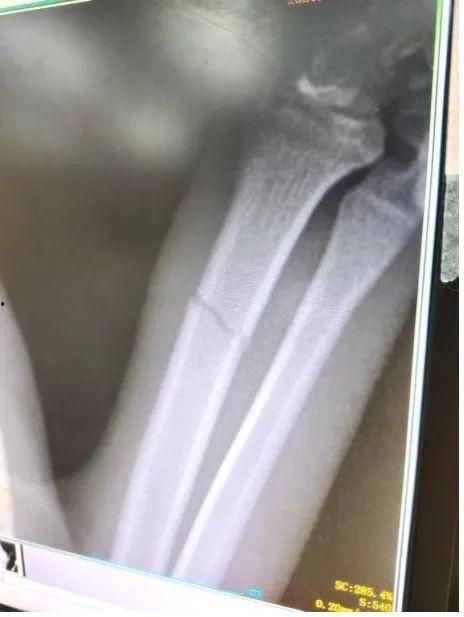

2022年,娱乐圈的明星们似乎特别容易遭遇骨折的“硬伤”。从影视演员到歌手,从体育明星到网红,骨折成了他们职业生涯中的一大挑战。那么,这些明星们究竟是如何受伤的呢?